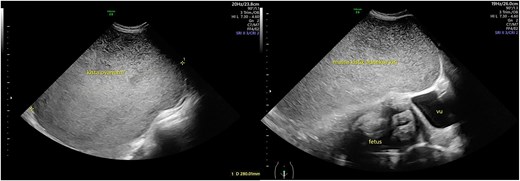

A 26-year-old woman with 34 weeks of gestational age, came to the polyclinic with the symptoms of right abdominal discomfort referred from another hospital with a massive ovarian cyst in pregnancy. The ovarian cyst was first detected during 28 weeks of pregnancy during her first ultrasound examination. Her abdomen was distended with a palpable mass until processus xiphoideus. Ultrasound examination showed the uterus was pushed to the right side of the abdomen with a singleton live fetal breech presentation. The fetus was around 34-weeks of gestational age, with estimated fetal weight of 2299 g, normal amniotic fluid index, and no Doppler abnormality. The ovarian cyst was unilocular from the left adnexa containing homogenous echogenocity fluid with a diameter of 28 cm, suspected of a mucinous cyst (Figs 1 and 2). A follow-up ultrasound examination showed a similar result for the cystic mass, however, the baby’s growth was declining. The Ca-125 value was below 15. Since the mass was suspected of benign origin, a Cesarean section (CS) was planned at term continued with unilateral salpingo-oophorectomy. There is no urgency to do a earlier termination of pregnancy since the fetus cardiotocography and doppler studies is within normal limit.

Ultrasound view of the cystic mass. The mass was unilocular without a solid part with a diameter of 28 cm.